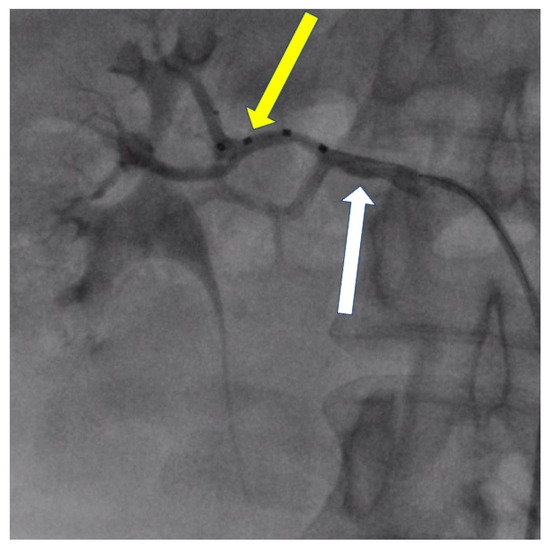

- Możeńska, O.; Rosiak, M.; Gziut, A.; Gil, R.J.; Kosior, D.A. First-in-man experience with renal denervation of multiple renal arteries in a patient with solitary kidney and resistant hypertension. Pol. Arch. Intern. Med. 2017, 127, 60–62. [Google Scholar] [CrossRef]

- Tokarek, T.; Rajtar-Salwa, R.; Rzeszutko, Ł.; Bartuś, S. Long-term benefit of redo sympathetic renal denervation in a patient with resistant hypertension. Postep. Kardiol. Inter. 2021, 17, 239–241. [Google Scholar] [CrossRef] [PubMed]

- Atas, H.; Durmus, E.; Sunbul, M.; Mutlu, B. Successful accessory renal artery denervation in a patient with resistant hypertension. Heart Views 2014, 15, 19–21. [Google Scholar] [PubMed]